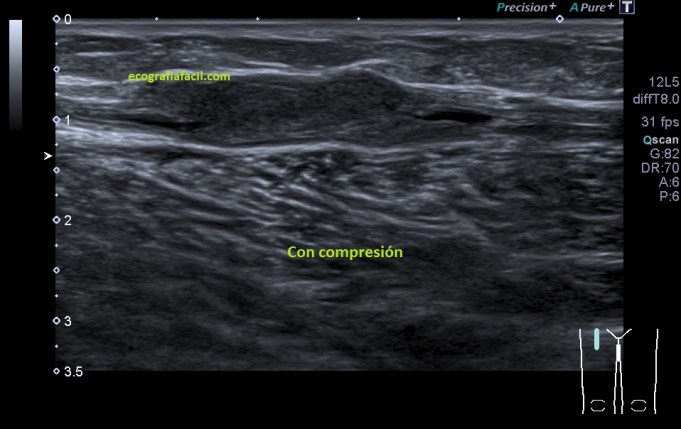

Recorrí de craneal a caudal la estructura y vi que el contenido se mantenía por algunos centímetros, comprimí la estructura, hice el estudio en la misma localización, con y sin compresión, imágenes 5 y 6, supe entonces que era una vena y que el contenido hacía que en algún punto la vena no se comprimiese. Puse doppler color y pulsado,imagen 4, comprobando si el vaso estaba permeable al menos parcialmente y efectivamente, y «escuchando» el sonido del paso de la sangre en ese punto. Ojo siempre a la correcta angulación del Doppler, en este caso no es correcta, solo quería certificar que era una vena, y así era.